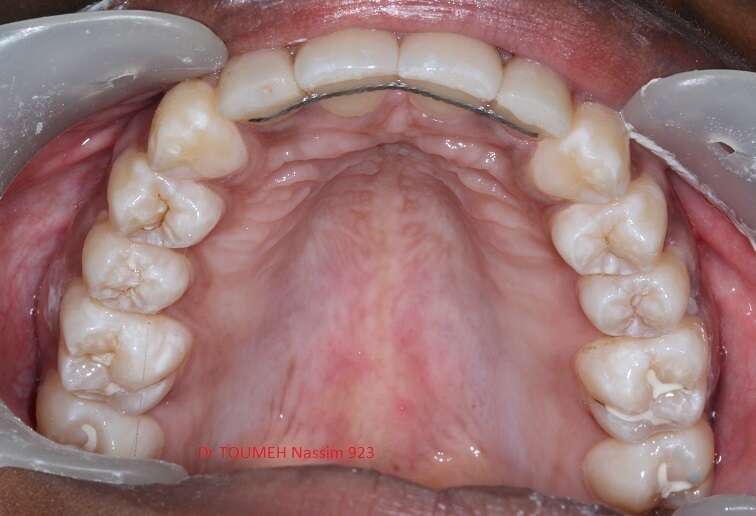

Latérales naines et orthodontie

la forme des dents influence grandement l’esthétique du sourire

La malformation des incisives latérales en est l'illustration

Le traitement consiste à redresser les dents à l'aide d'un appareil orthodontique (Multiattaches) et à redonner une forme normale aux dents malformées.

Dans ce cas présenté des couronnes provisoires en résines ont été posées.

Après